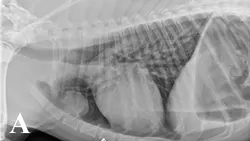

Thoracic radiography and abdominal ultrasonography were performed to screen for an inciting cause of MG. Thoracic radiographs (Figure 1) showed a well-circumscribed, spherical-to-ovoid cranial mediastinal mass and moderate megaesophagus. Thymoma was considered the most likely cause. There was no evidence of aspiration pneumonia. Abdominal ultrasonography was unremarkable.

Figure 1. Lateral (A) and ventrodorsal (B) thoracic radiographs showing a round, circumscribed mass in the cranial thorax and moderate megaesophagus.